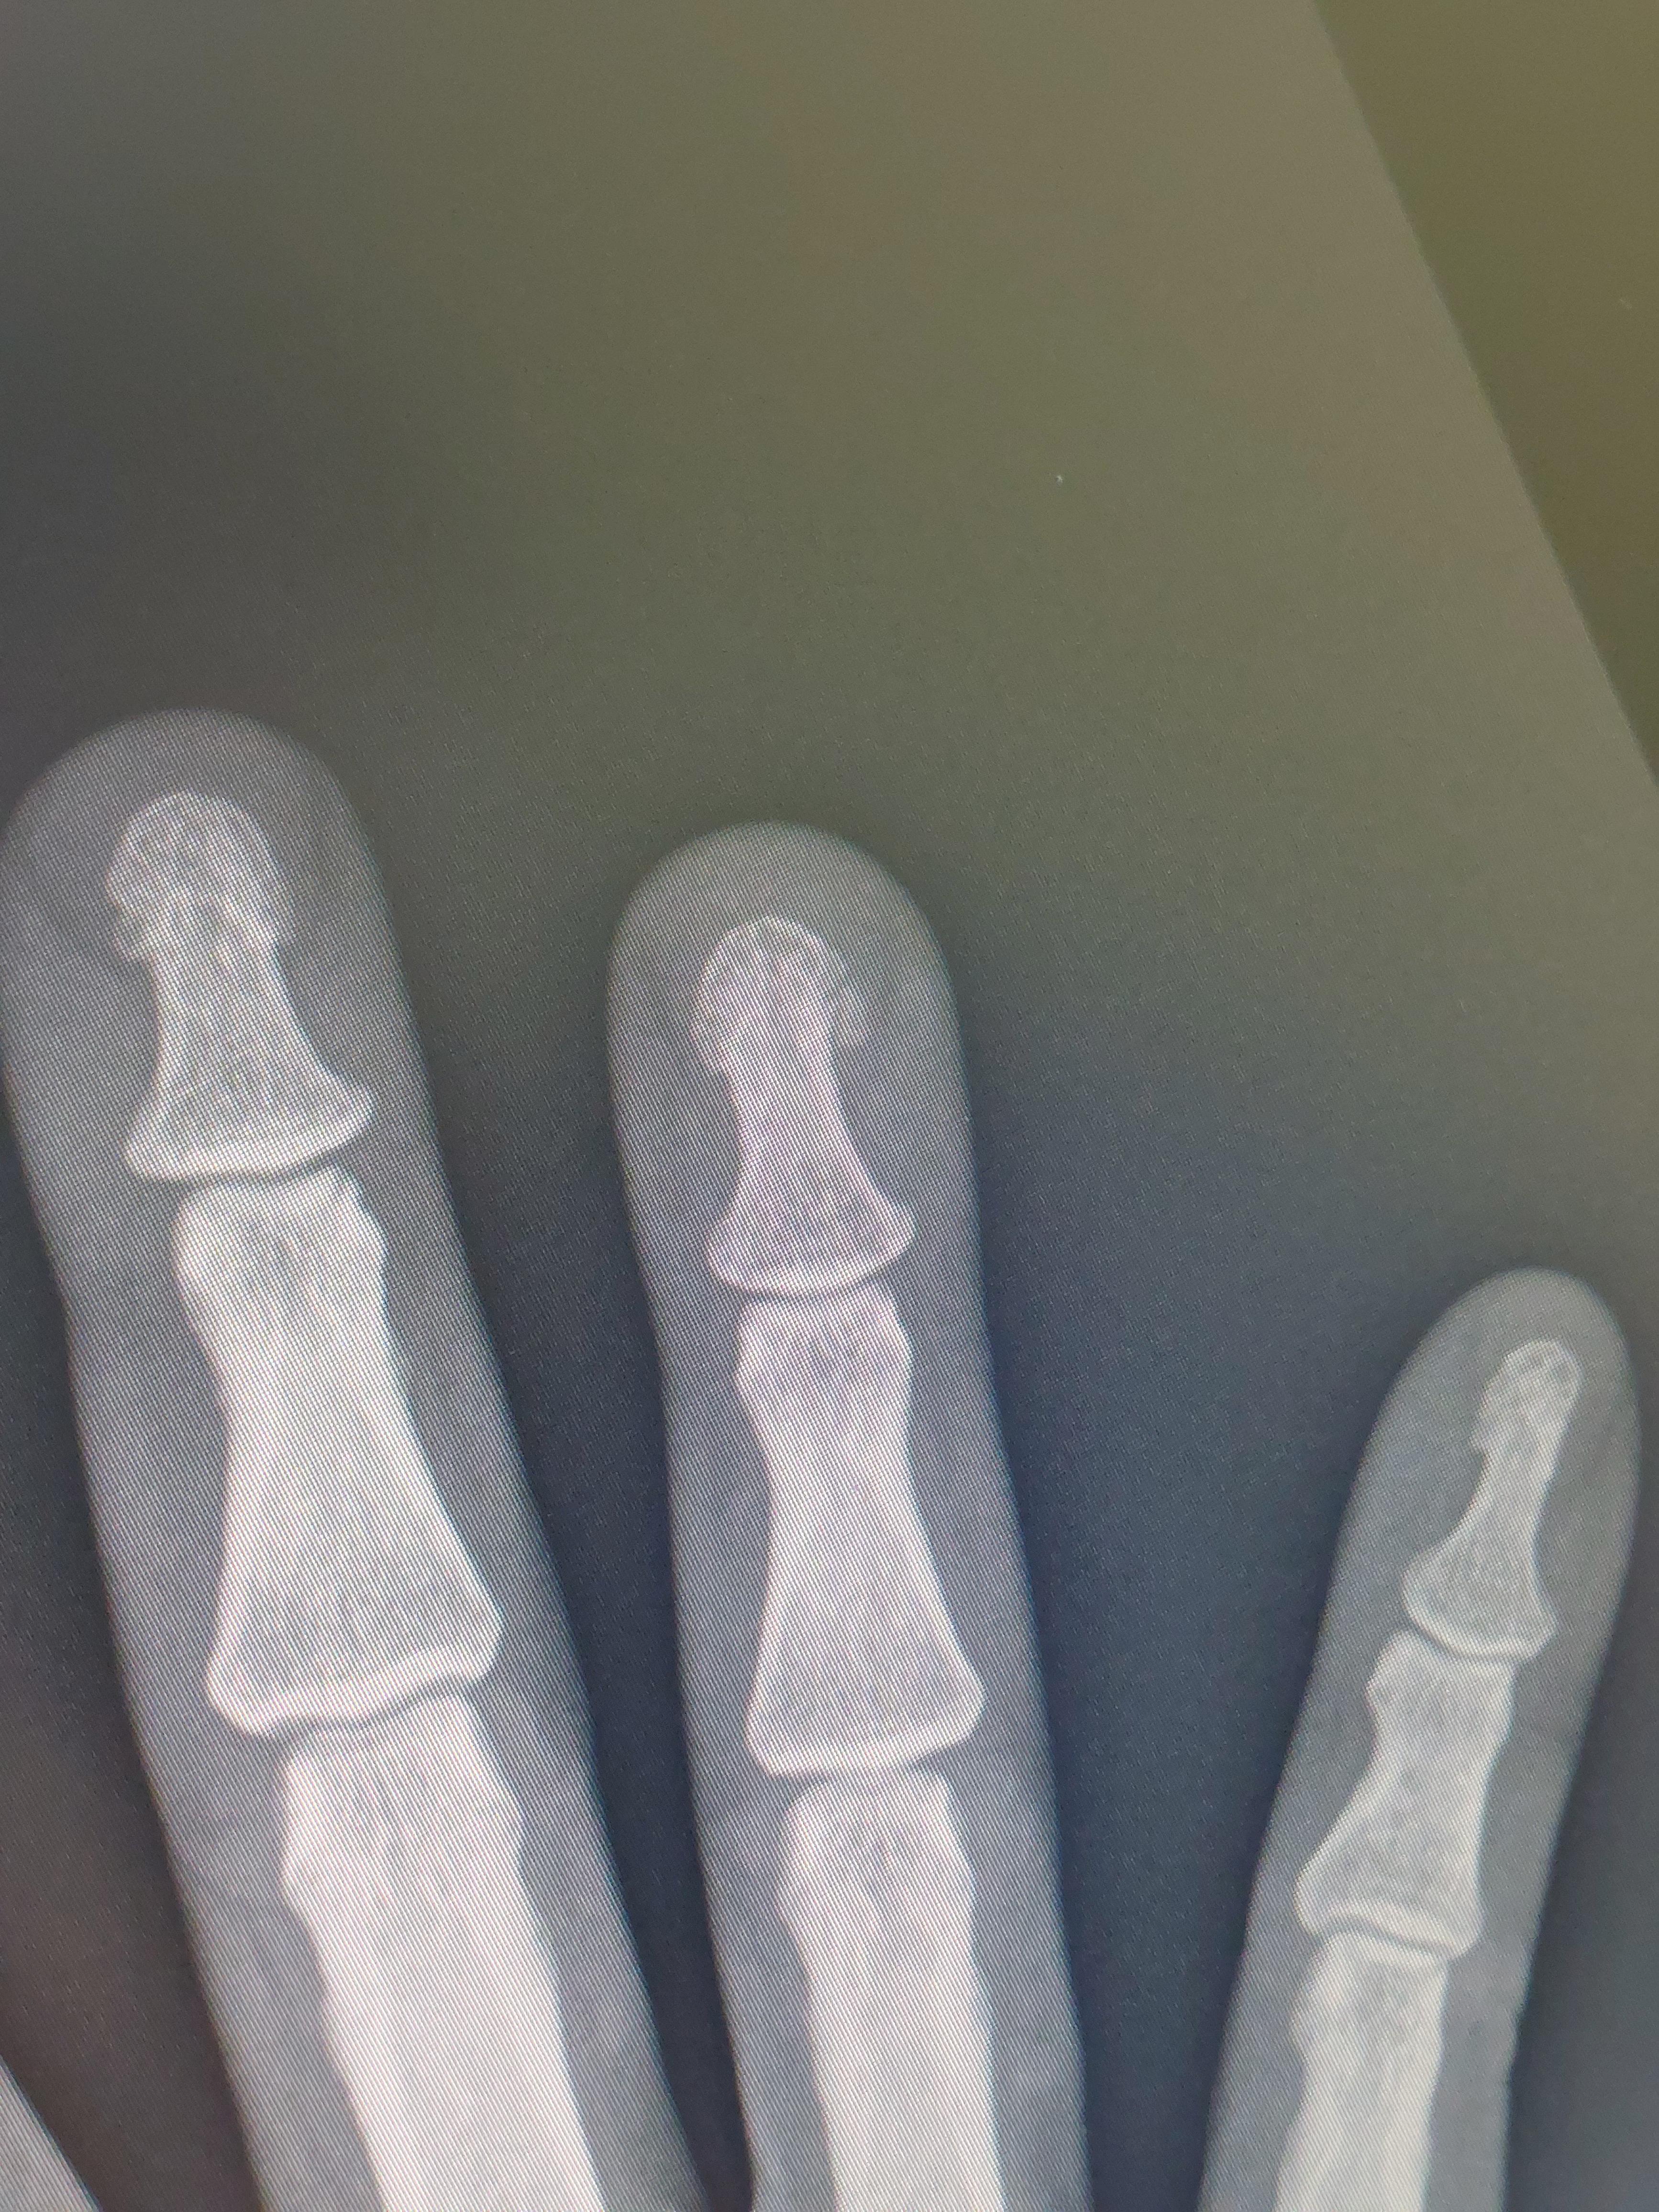

잠시후 엑스레이 찍으니

약지 손톱 아래 뼈가 깨졌다고 의사 선생님이 말씀하시네요.

아마도 인대와 힘줄 근육 손상도 동반되었으 것으로 보이니 정밀검사를 받아라 하십니다.